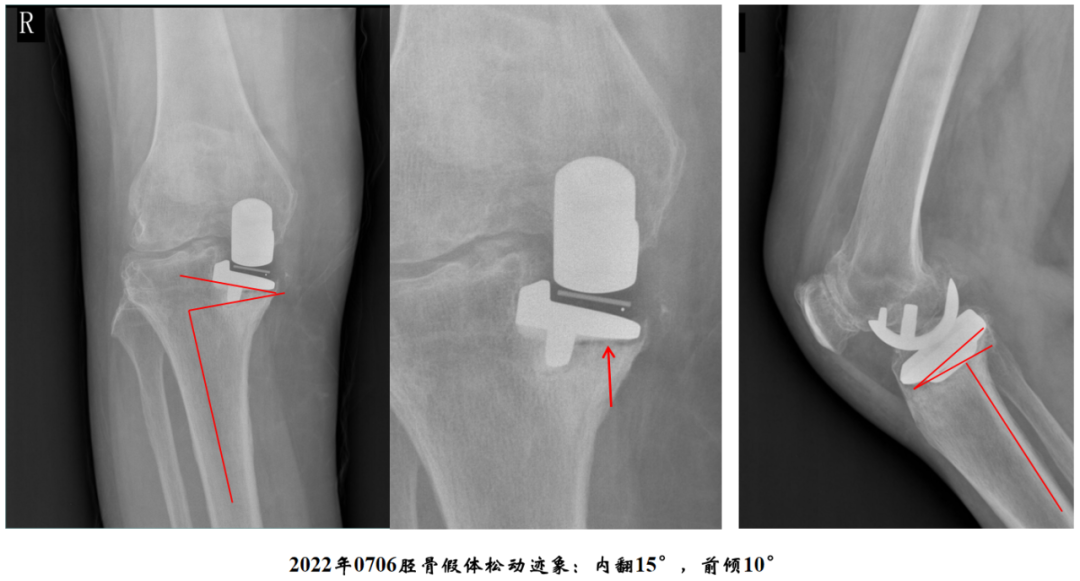

病例2:胫骨假体松动

病例2:单髁翻单髁